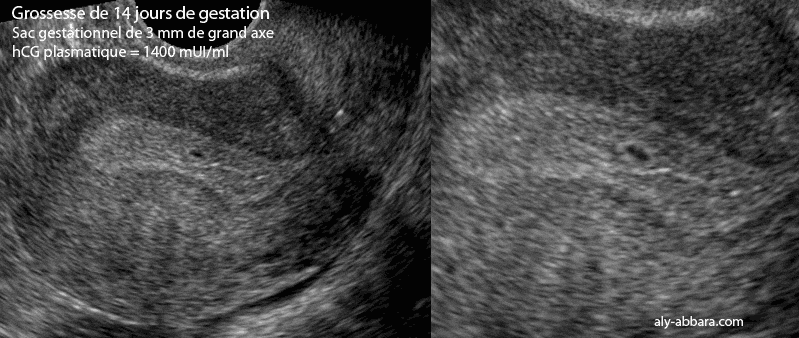

Coupe échographique sagittale montrant un utérus gravide avec la présence d'un sac gestationnel d'une grossesse débutante âgée de 14 jours de gestation ; on observe la présence d'un sac gestationnel intra-utérin de 3 mm de grand axe, et bien sûr, aucune structure embryonnaire ne peut être identifiée à cet âge de grossesse.

L'âge de la grossesse a été calculé grâce à la date connue de l'ovulation et confirmé par la datation échographique ultérieure, après avoir mis en évidence l'embryon et la longueur crânio-caudale qui a été mesurée deux semaines plus tard.